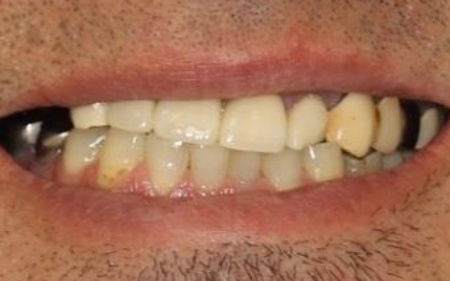

50代男性 バランスが崩れた噛み合わせをインプラント治療と被せ物治療で改善した症例

「30代から歯科医院に通っていたが、歯が痛むときだけしか受診しなかったせいか、歯が折れて欠損部が増え、噛みにくくなってしまった。また、今までいくつかの歯科医院を受診したが解決が難しく、こちらを受診した」とご相談いただきました。

拝見したところ、右上奥歯4本が欠損しており、その影響で全体の噛み合わせのバランスが崩れていました。

加えて、噛んだときに上下の歯の中心がずれており、顔貌のゆがみにもつながっています。

欠損部が多い状態が長期間続いたことで噛み合わせが低く、新しい歯を入れるための高さも不足していました。

また、右上前歯も1本欠損しており、両隣の歯を土台として橋を渡すように連結した被せ物「ブリッジ」が装着されていましたが、土台となっている右上前歯2本(中切歯、犬歯)が割れており、温存が難しい状態です。

さらに、劣化してうまく適合していない被せ物、詰め物、既存のインプラントが複数見られ、これらも噛み合わせを乱す原因となっていました。

加えて全体的に歯周病も進行しており、骨が溶けている部分も確認できます。